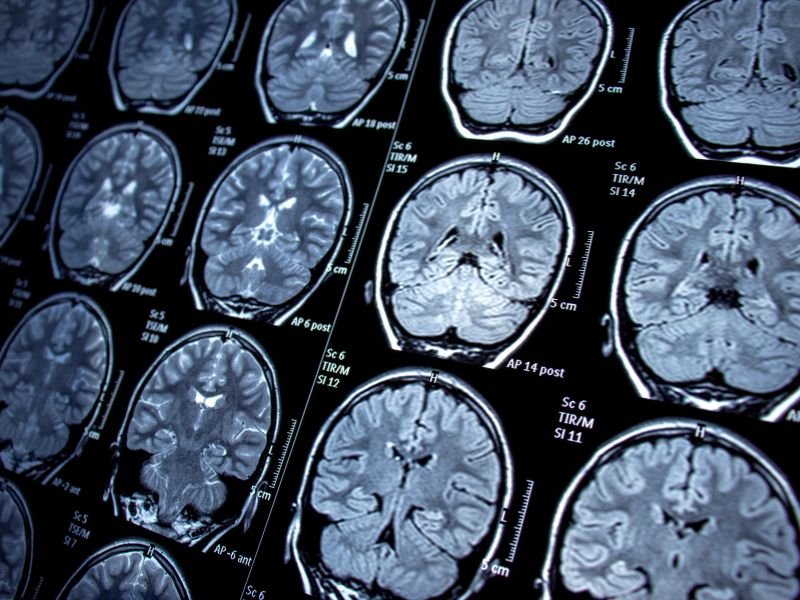

Tratamento de Aneurisma Cerebral em Tubarão SC O aneurisma cerebral é uma dilatação anormal de uma artéria no cérebro, que pode levar a complicações graves, como hemorragias. O tratamento desse tipo de condição é fundamental